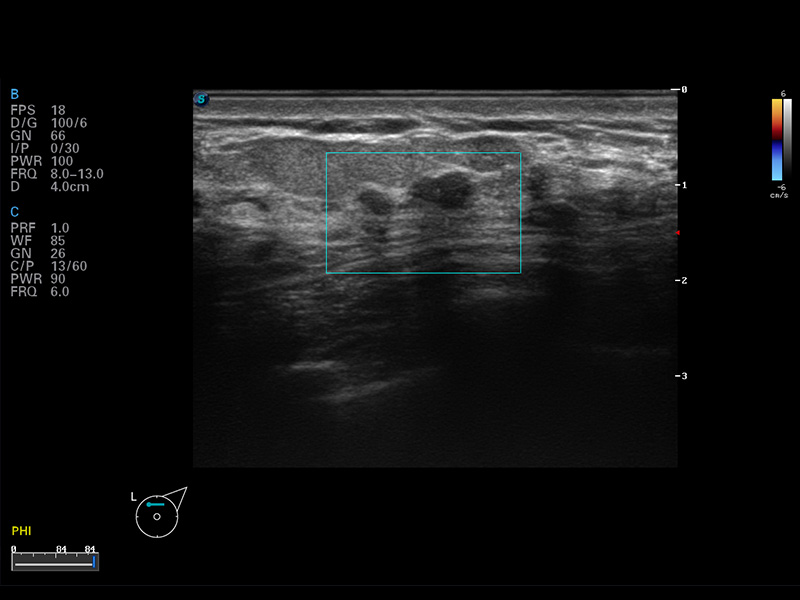

谐波成像

空间复合成像